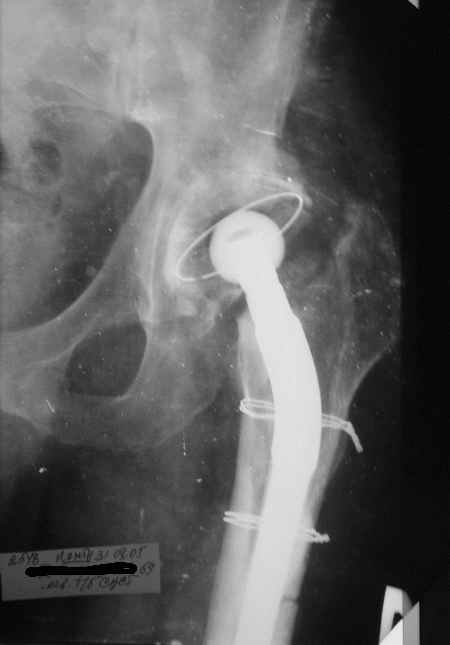

Уважаемые коллеги, Мужчина, 69 лет, в декабре 2004 г перенес тотальную цементную артропластику

Через 3 мес после операции на фоне прогрессирующих болей в средней и проксимальной третях бедра при нагрузке возникли резкие боли и появилось опухолевидное болезненно образование. Процесс сопровождался резким одномоментным укорочением ноги.

В феврале 2005 г. выполнена ревизионная артропластика, завершившаяся прогрессировавшим в течение 1-2 мес укорочением ноги. В настоящее время ходит только с костылями, при движениях в тазобедренном суставе испытывает резкие боли, ощущает хруст. Попытка осевой нагрузки бедра сопровождается ощущением "перемещения поршня" и заметным по внешним ориентирам укорочением левой ноги на 1-1,5 см.